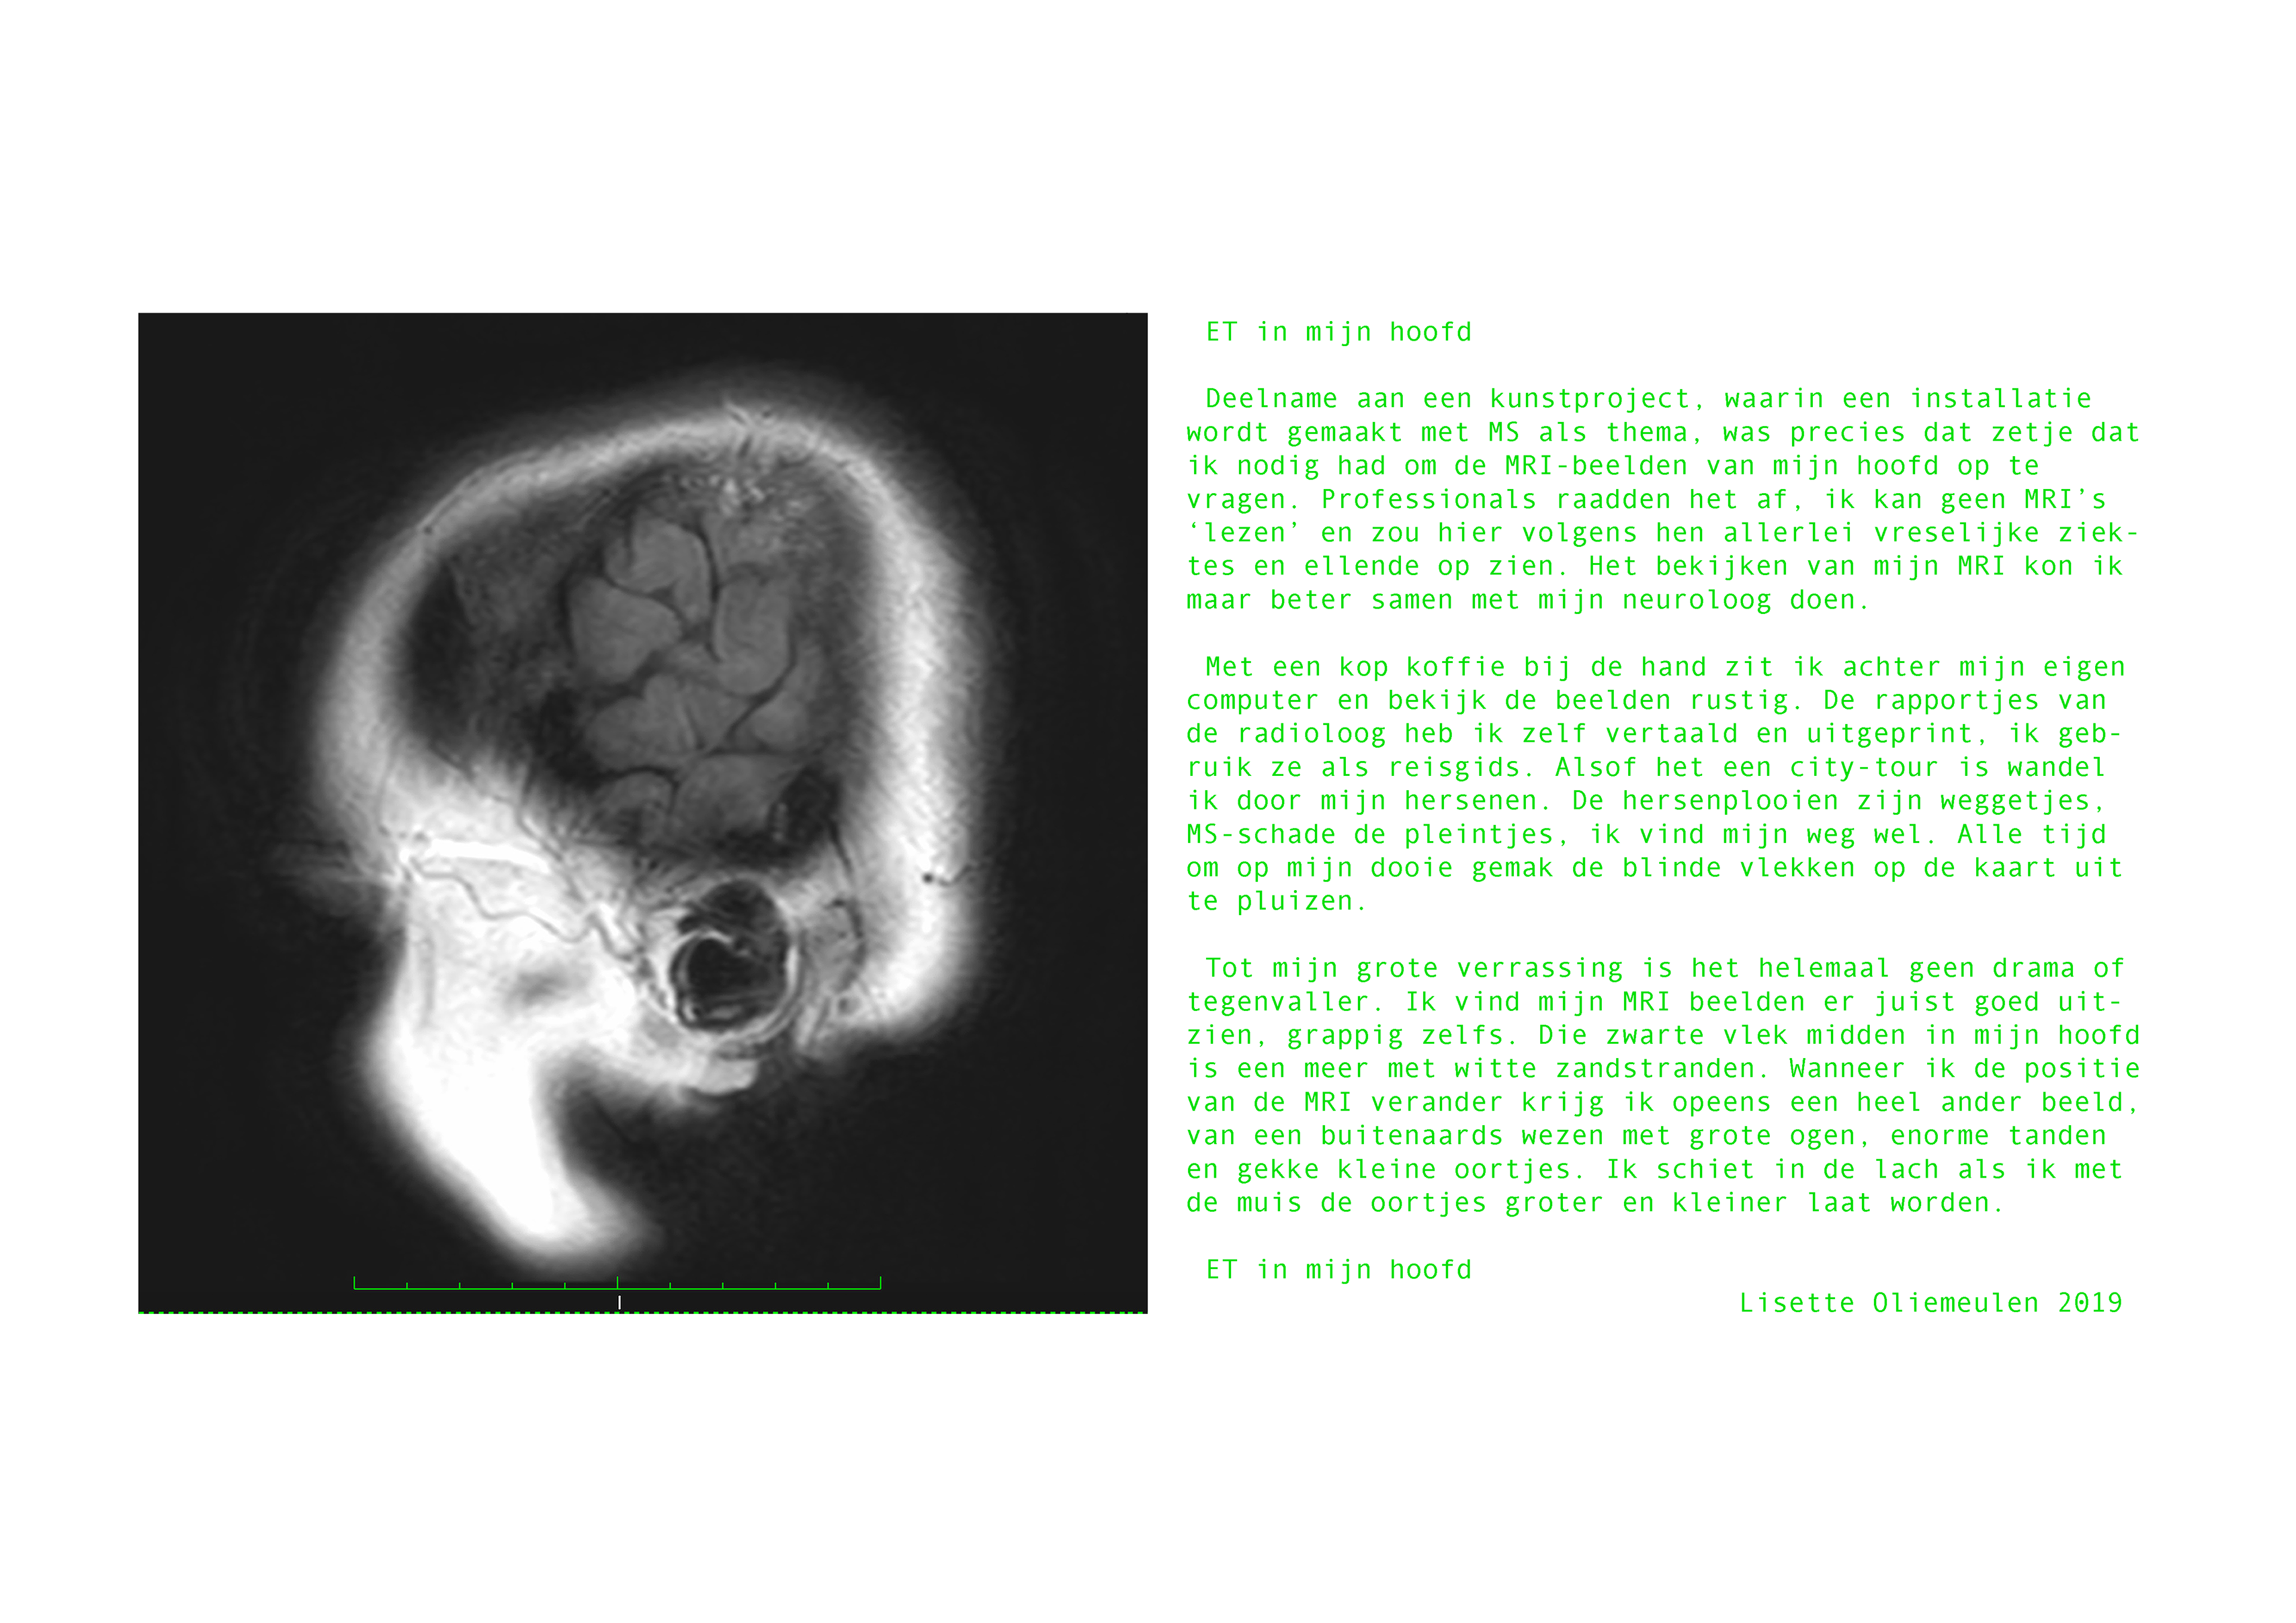

In een gezamenlijk kunstproject met drie andere vrouwen met MS, Marta Lameris, Andrea van Sloterdijck en Lisette Oliemeulen, onderzocht ik de veilige ruimte voor het delen en onderzoeken van persoonlijke ervaringen met de chronische ziekte doormiddel van dialoog en verbeelding. Centraal stonden de vragen;